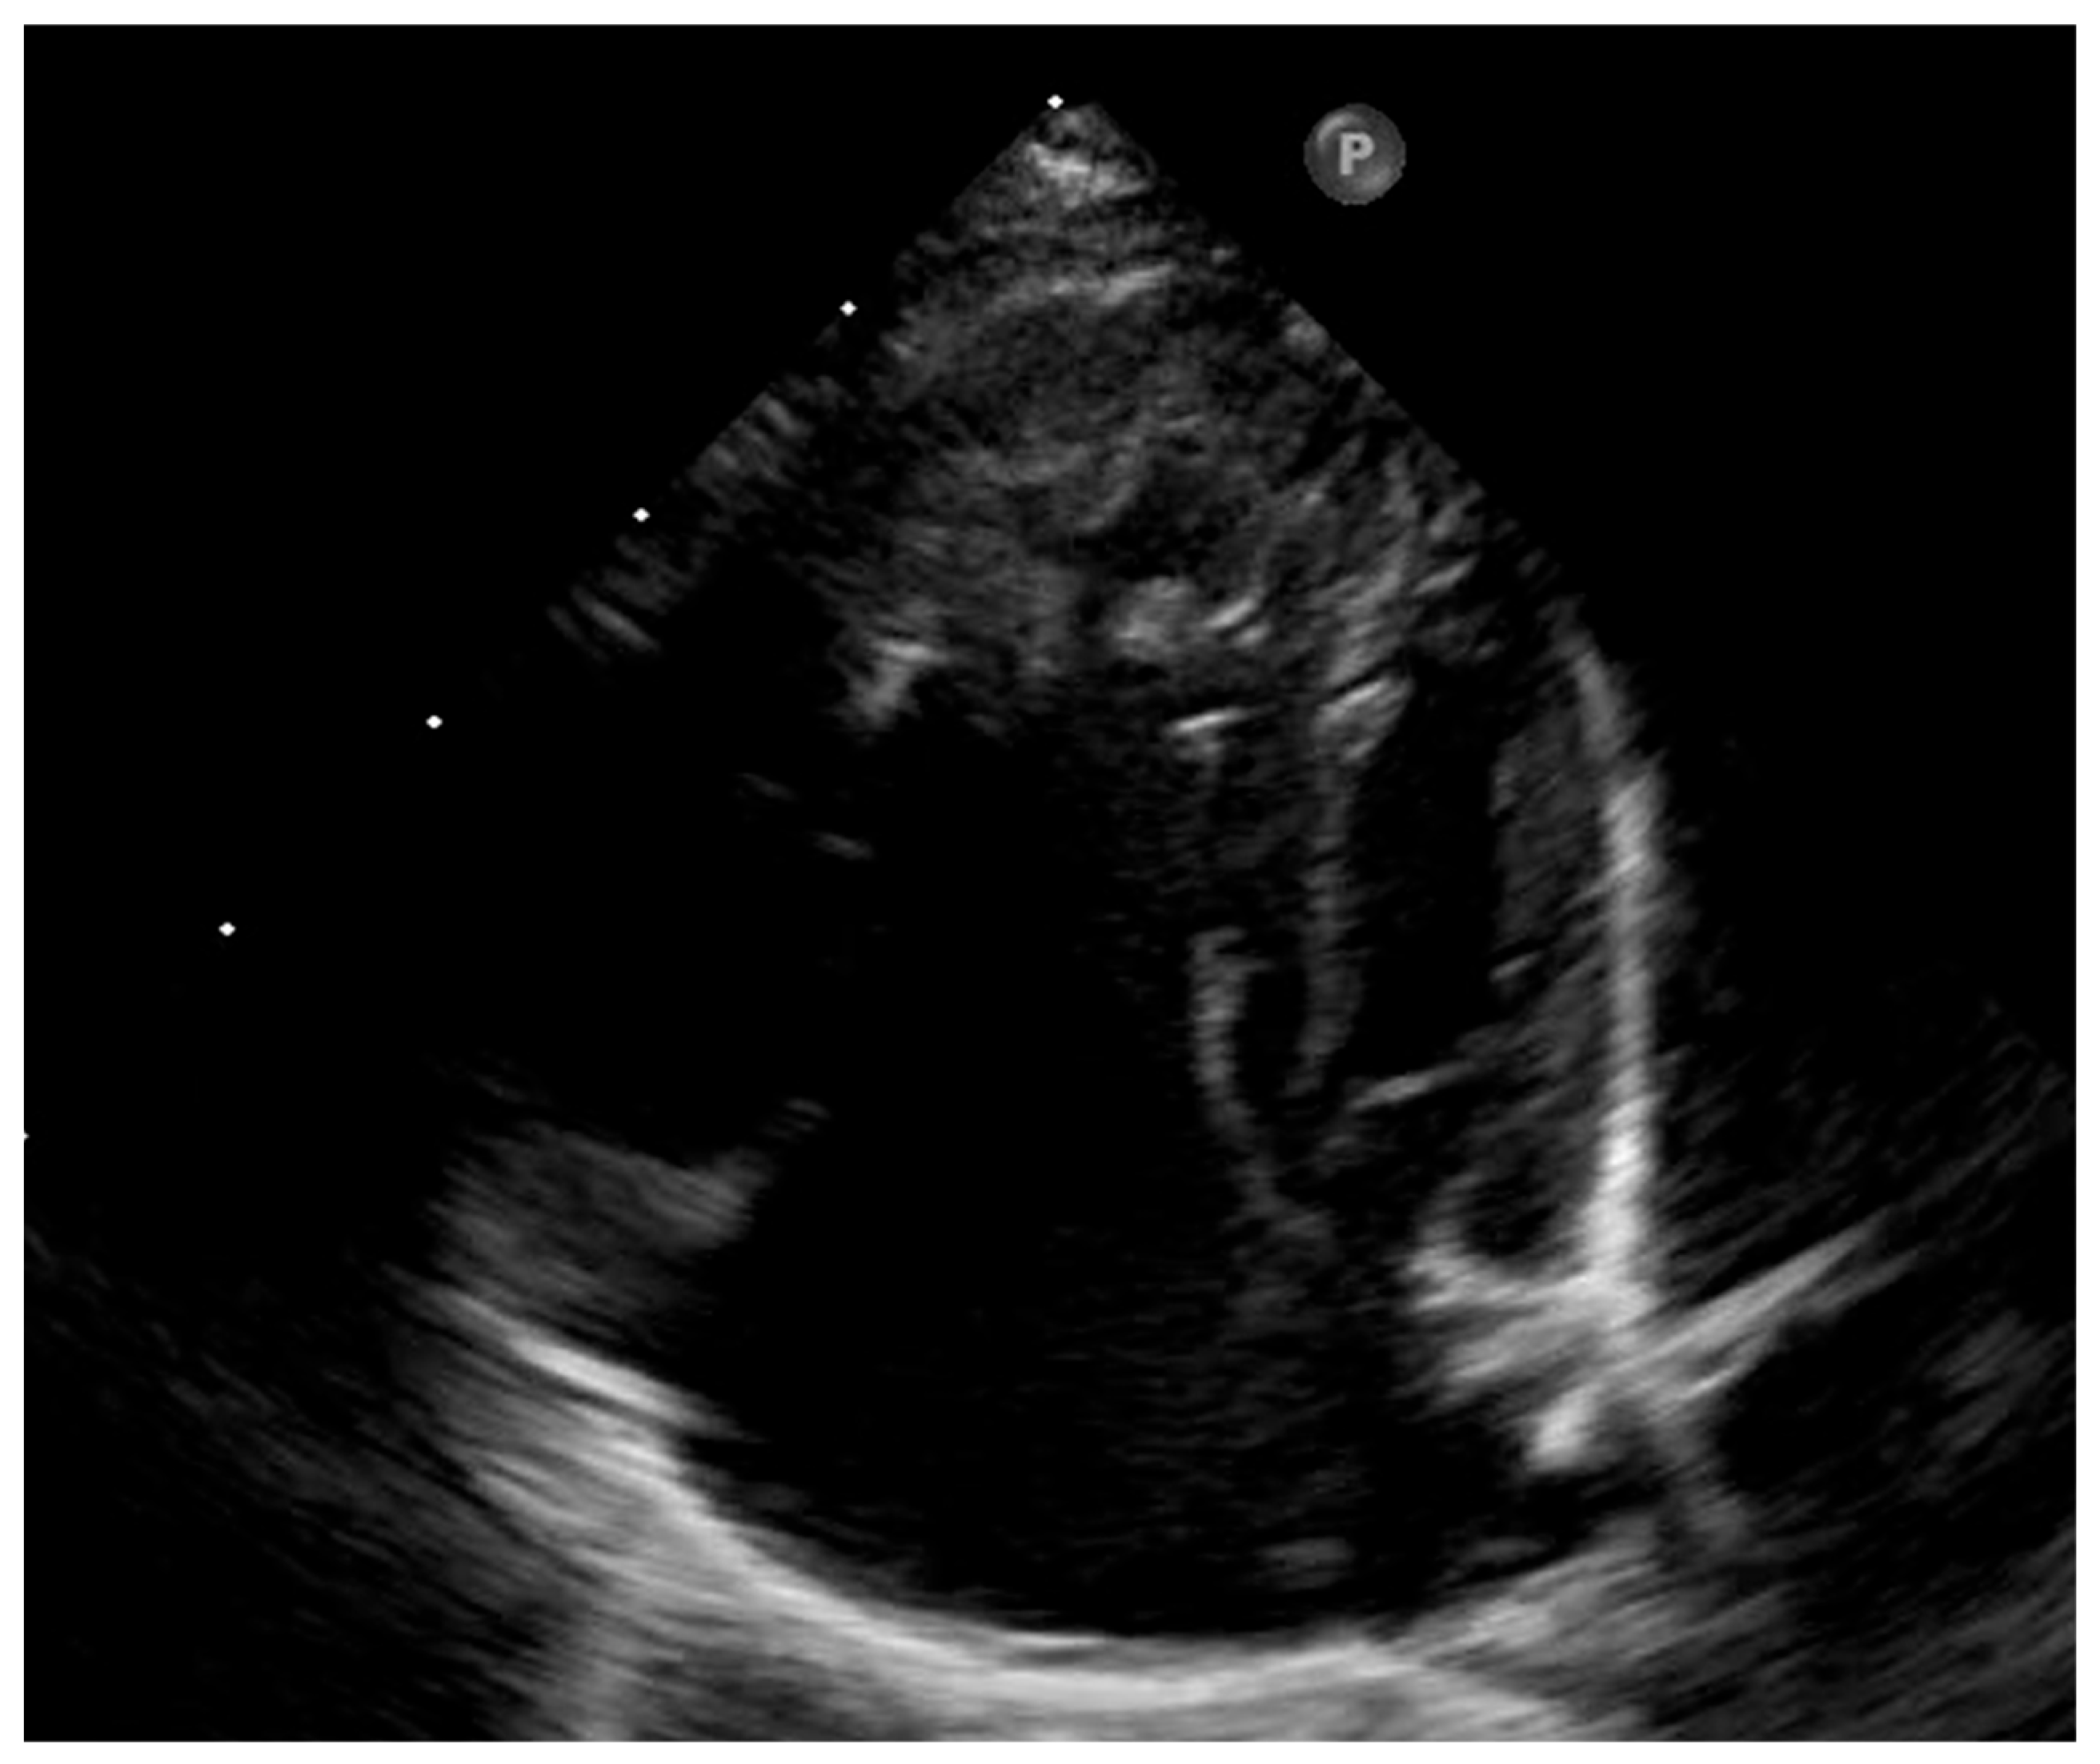

| Parameter | First Day of Life | Day 1 Postoperative | 2-Year Follow-Up |

|---|---|---|---|

| Mitral valve annulus (mm) | 8.5 | 8.7 | 15.4 |

| Mitral valve z-score | −4.1 | −4.0 | −0.6 |

| Aortic valve annulus (mm) | 5.9 | 6 | 10 |

| Aortic valve z-score | −3.5 | −3.5 | +1.3 |

| Left ventricle peak global longitudinal strain | −18.3% | −18.7% | −21.9% |

| Mean transmitral gradient (mmHg) | 3 | 4 | 4 |

| Atrial septal defect (mm) | 6 | 3 | 3 |

| Direction of atrial shunt | Left-to-right | Left-to-right | Left-to-right |

| Estimated pulmonary systolic pressure (mmHg) | 54 | 42 | 20 |